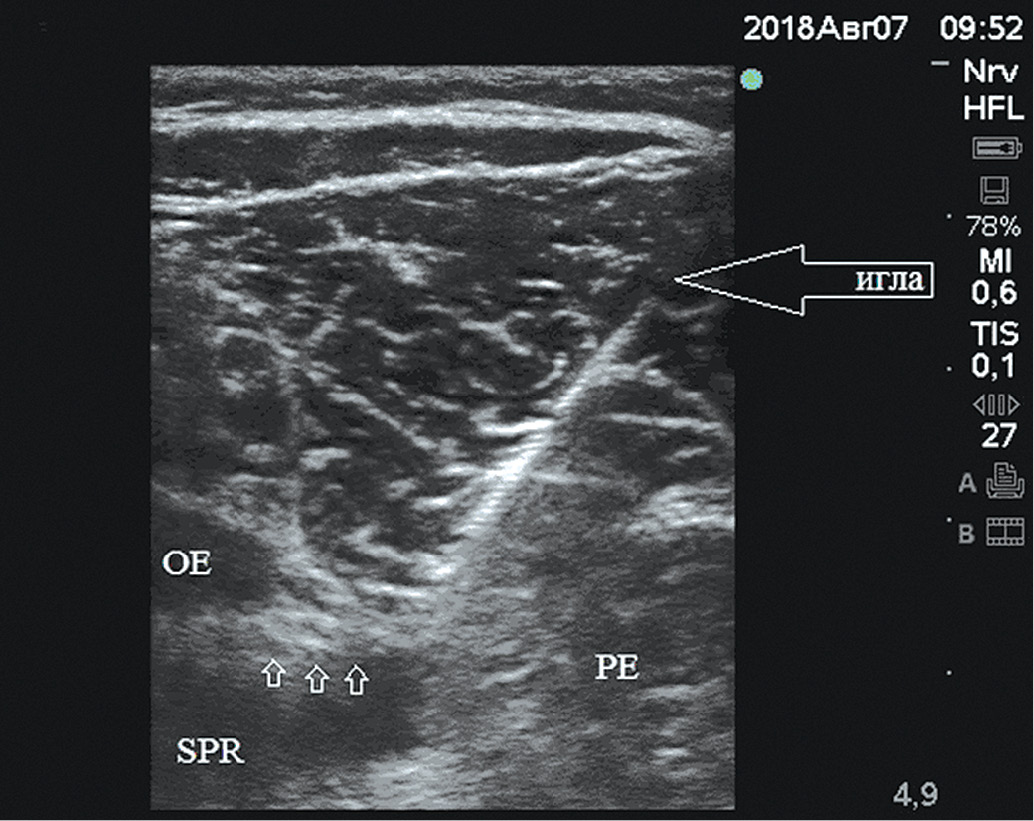

В качестве ориентиров определяли верхнюю ветвь лобковой кости, гребенчатую мышцу, наружную запирательную мышцу, находили запирательный нерв – гиперэхогенная структура овальной формы. Изолированную иглу, подключëнную к нейростимулятору, вводили по методике «в плоскости датчика» (рис. 3).

Рис. 3. Ультразвуковая картина блокады запирательного нерва: нерв обозначен стрелками. SPR – верхняя ветвь лобковой кости, OE – наружная запирательная мышца, PE – гребенчатая мышца

Стимуляцию нерва начинали с силой тока 0,8 мА, после получения сокращений приводящих мышц снижали силу тока до 0,3–0,5 мА. Убедившись, что при силе тока 0,2 мА сокращения отсутствуют, вводили 2% раствор лидокаина 10 мл. Распространение анестетика вокруг нерва контролировали с помощью ультразвуковой картины.